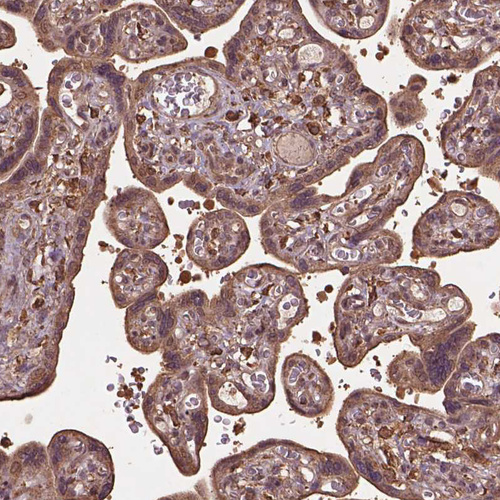

Immunohistochemical staining of human testis shows strong cytoplasmic positivity in Leydig cells.